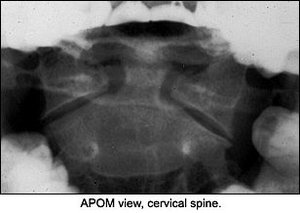

The lateral view isn't very helpful, but the APOM demonstrates a slight depression of the lateral mass of C2 on one side compared to the opposite side. Other than that finding, nothing really appears to be significant. If you didn't have the history, would you have taken the X-rays? If you didn't have the history and the clinical findings, would you have noticed the difference in the lateral masses of C2? It's difficult to say. I'm not certain I would, but the patient had significant discomfort.

So, what would you do now with this information? Perform orthopedic tests, or would you do further imaging? I decided on more imaging because I'm into radiology. I really didn't want to do any orthopedic tests on the patient because having him run through simple range of motion of the cervical spine aggravated his symptoms, so I ordered a CT of the cervical spine. Upon review of the X-rays, we can now see that the APOM was telling us the answer we couldn't see clearly.

On the CT scan through the C1-2 vertebrae, note the fracture through the dens and the lateral mass of C2. (That was the depression we saw on the APOM of the lateral mass.) Should we look at the APOM view again?

This view above evaluates C1-C2, which cannot be visualized clearly on the lateral. The most important element to check is the alignment of the lateral masses of C1. The intervertebral space should be symmetric. The dens can also be evaluated for fracture in this view, but occasionally overlying shadows may give the false impression of a dens fracture (Mach effect). Correlate the findings with the lateral view of the cervical spine. The incidence of fractures to the axis is about 6 percent, and over 50 percent of those fractures involve some part of the dens.